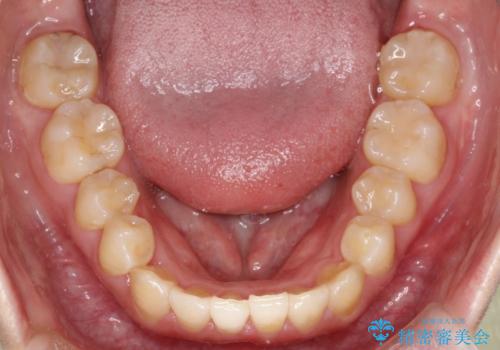

前歯が前後反対にかんでいる インビザラインによる矯正

しっかりとマウスピースを使用していただけたので、順調に治療を終えることができました。

- 前歯のがたつきを気にされて来院されました。

上顎の前から二番目の歯が内側に入り込んでおり、前後反対にかんでいる状態でした。

歯と歯の間にわずかに隙間を作り並べる計画としました。